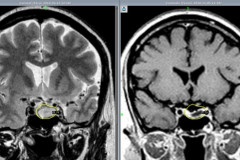

В МЦ «Астхик» сотрудничестве с благотворительным фондом «Вива» внедряют новый ме...

53-летняя женщина в Ереване родила мальчиков-близнецов после 12 лет бесплодия (ф...